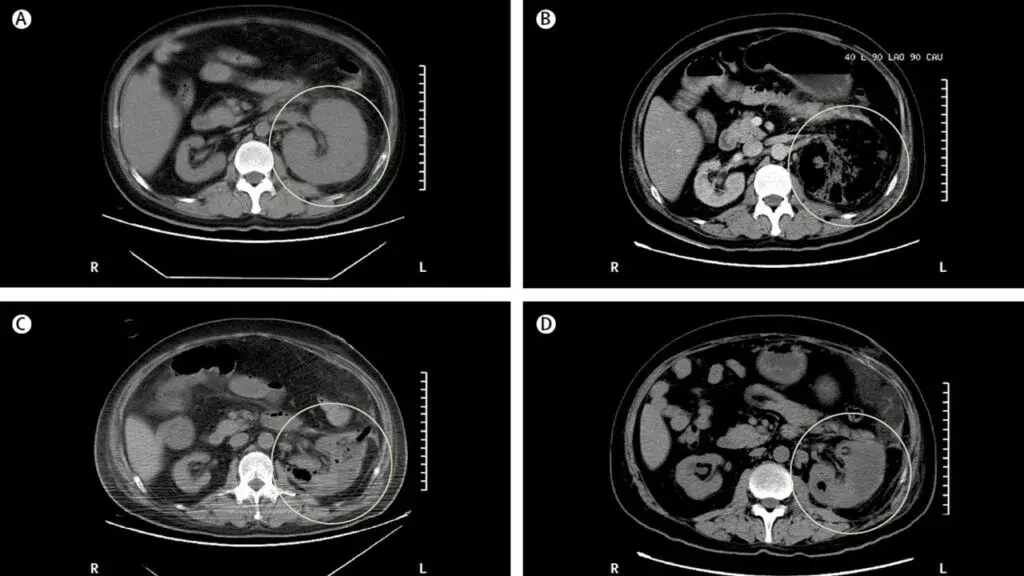

Um homem de 39 anos foi internado no hospital com história dia com dor no flanco esquerdo e tontura há um dia. Paciente tinha antecedentes de diabetes mal controlado e nefrolitíase obstrutiva à esquerda. Após avaliação inicial a TC do abdome mostrou aumento do tamanho do rim esquerdo devido gás no parênquima renal, espaço perirrenal e veia renal. Foi instituído tratamento com antibióticos e realizado de cirurgia aberta (elevado risco de embolização). O paciente evoluiu com melhora clínica e radiológica, TC de controle após 04 dias já mostrou redução do gás e do volume renal. Qual é o diagnóstico?

Caso típico de **pielonefrite enfisematosa** publicado no The Lancet ([link](https://www.thelancet.com/journals/lancet/article/PIIS0140-6736(19)30771-8/fulltext)). Os casos geralmente são decorrentes de infecção por _Escherichia coli_ em pacientes com diabetes descompensado e obstrução do trato urinário. A glicose é um substrato para proliferação de bactérias fermentadoras (_Enterobacteriaceae_), que produzem gás carbônico e hidrogênio. **Fica a dica do elevado risco de embolização**. Quando presente obstrução, a desobstrução da via urinária é mandatória. Nos casos com gás no parênquima ou espaço perirrenal, é sugerido fortemente drenagem percutânea, caso o gás fique limitado ao espaço coletor (pielite isolada) o manejo com antibióticos é suficiente.